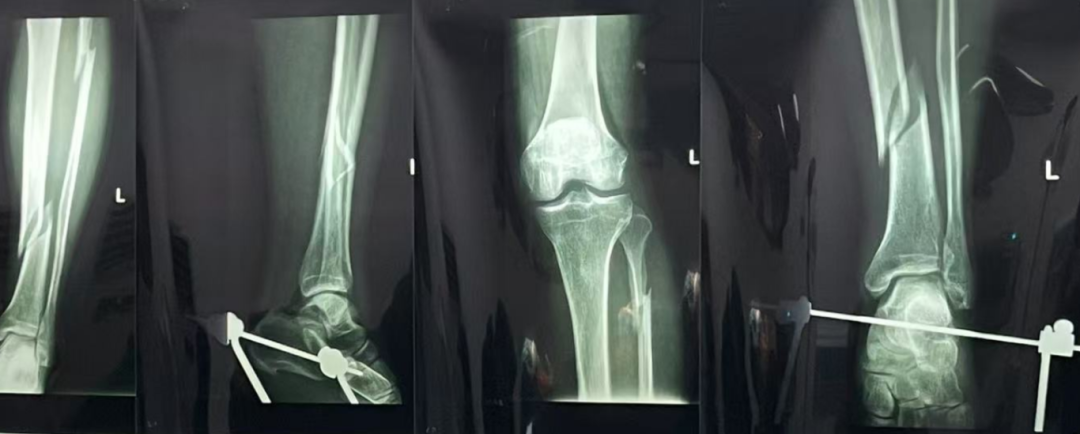

王女士,28岁,因遗传+长期穿高跟鞋导致踇外翻,外翻角度超40°,伴有疼痛和行走困难。她因工作需要,希望尽快手术。李龙飞医生评估后,决定采用微创手术,并制定详细术前准备和术后康复计划。手术顺利,王女士恢复良好,工作前已能正常行走,疼痛减轻。她感激地说:“李医生不仅治愈了我的脚,更让我在重要时刻能够自信地站出来。”